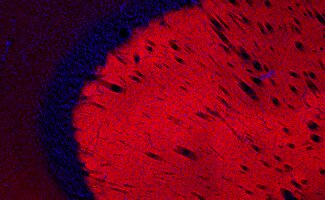

Dopamine Receptors

Dopamine receptors mediate signaling through interactions with the neurotransmitter dopamine.